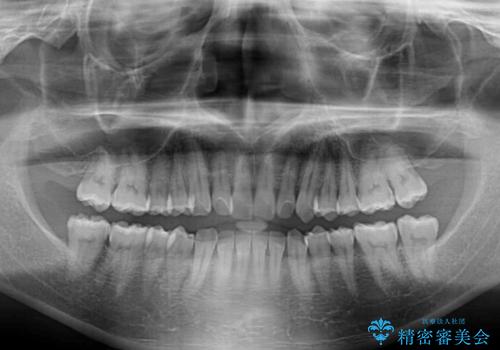

- 前歯のデコボコとクロスバイトを気にして来院された患者様です。

インビザラインでもワイヤー装置でも矯正治療は可能でしたが、煩わしい自己管理なしに短期間で治療を行いたいとのことで、目立たないワイヤー装置にて治療を行うこととしました。